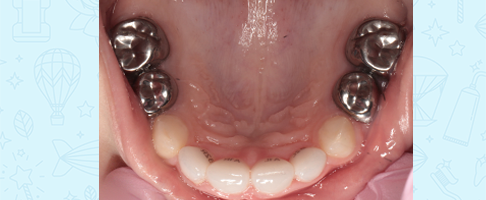

- восстановление молочных жевательных зубов коронками.

- восстановление фронтальной группы молочных зубов эстетическими циркониевыми коронками.